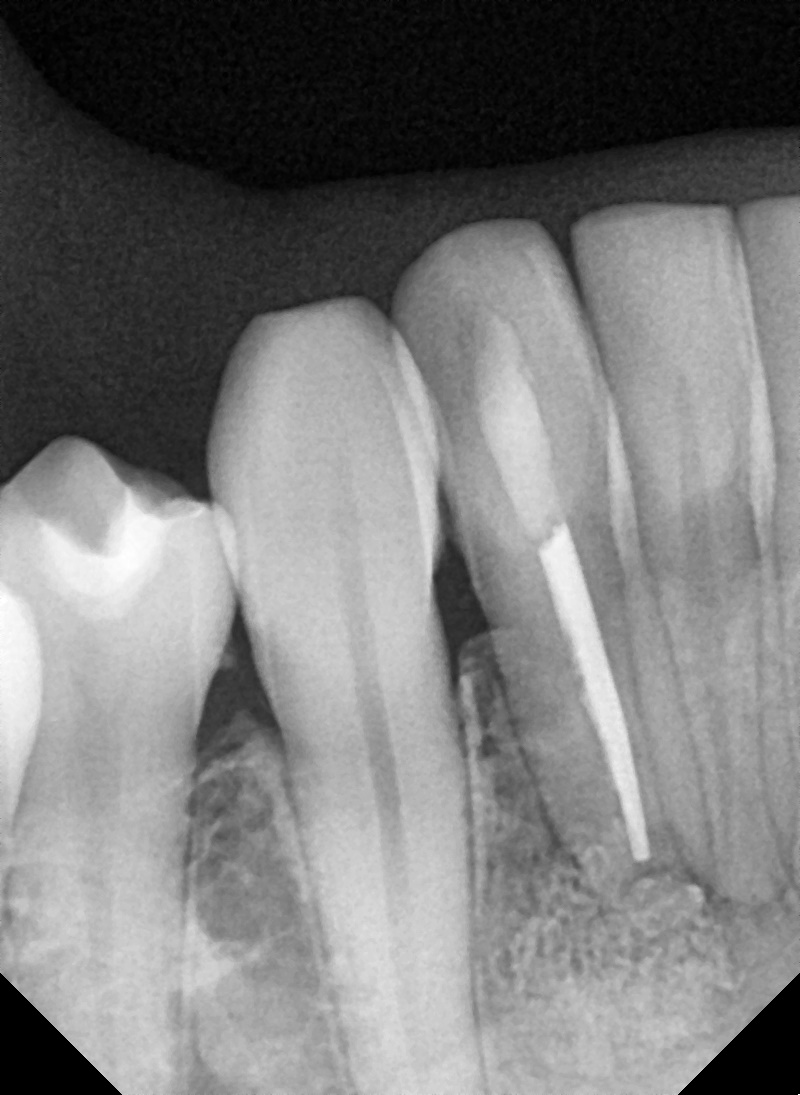

수술 전

수술 후

좌측 임플란트 흔들림 재수술 사례

전후사진